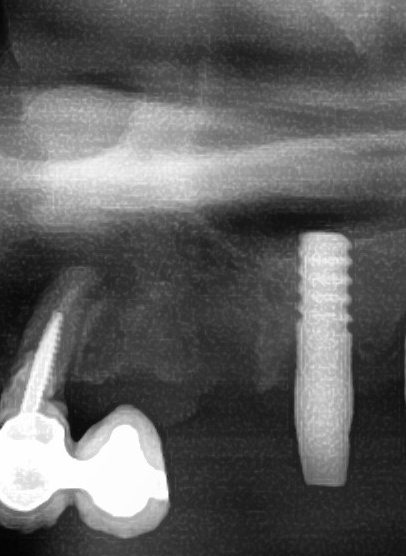

開けた穴に、専用道具を使ってネジを締めるように長さ2センチ程のインプラントを骨に埋め込んでいきます。

しっかりとインプラント埋め込まれた後は、動揺がないか、噛んだ時に当たらないかなどを確認して、最後にパノラマ写真を撮影して今回のオペは終了となりました。